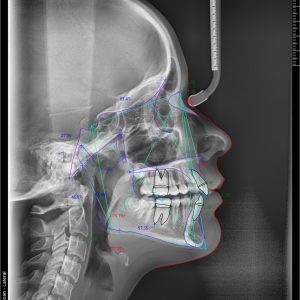

Telerendgen